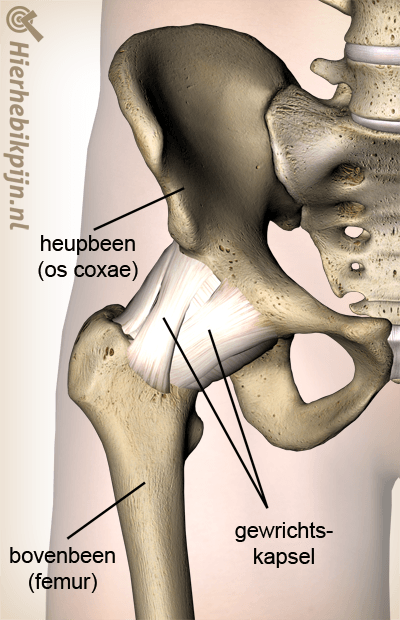

Heup